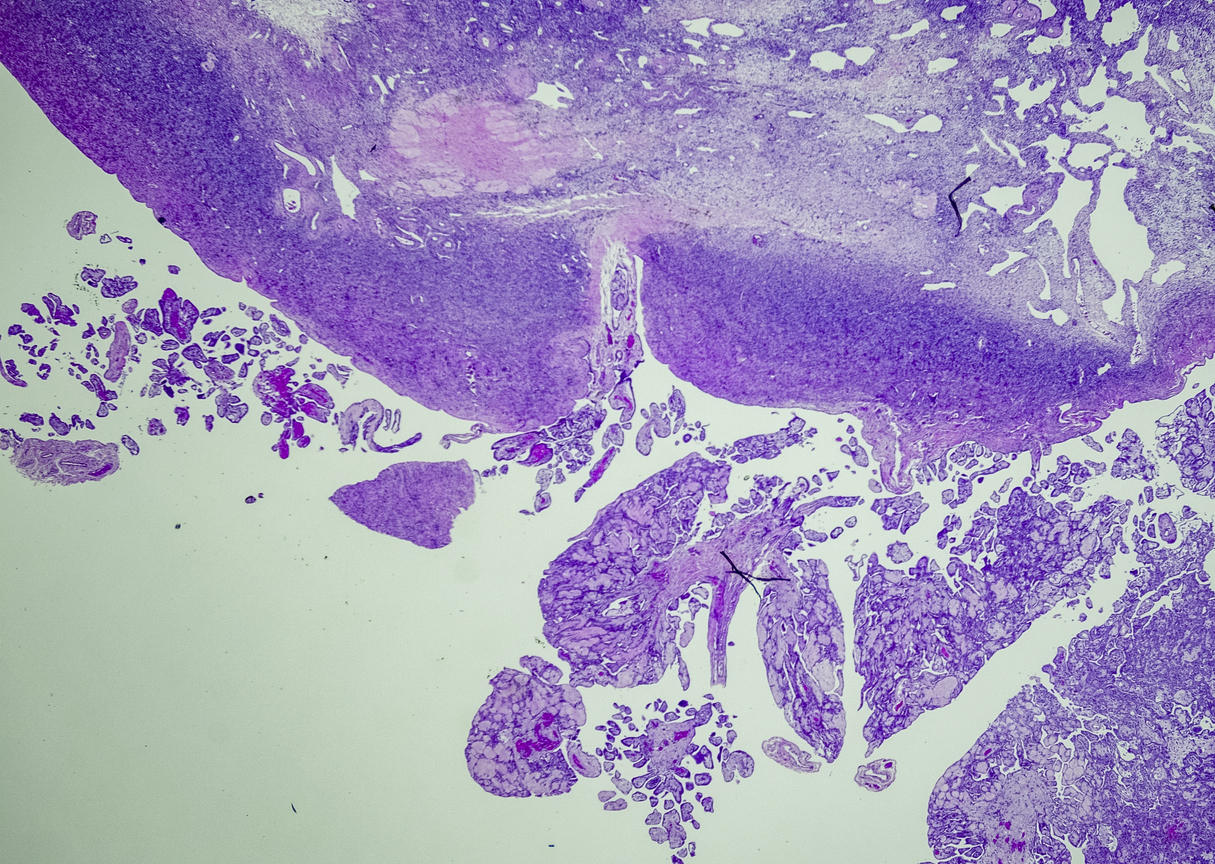

A tissue biopsy is the only way to diagnose epithelioid mesothelioma. This procedure involves taking samples of suspicious tissue. Pathologists examine the tissue samples under a microscope to identify specific cell characteristics.

Epithelioid mesothelioma cells clump together in groups and don’t tend to travel. These cell types are less likely to spread to other areas of the body. When a pathologist confirms the presence of specific cancer cells, an accurate diagnosis of your mesothelioma type can be made.

The first test for a patient with, symptoms related to mesothelioma will be going to their primary doctor, getting an x-ray or a CAT scan done. Based on the results from that, they may go through further testing such as a thoracentesis or paracentesis, which is where they drain fluid, whether it’s from the lining of the lungs or the peritoneal area, which is the abdominal area. The next step would be for a biopsy. The biopsy is a step where they confirm the diagnosis. This sample is sent to a pathologist who ultimately tests the sample taken out from the tumor and identifies it as mesothelioma.

And not just look at under microscope by any pathologist, but pathologist who has an expertise in making that diagnosis. Because even with a good sample of tumor, looking at it under a microscope, it can sometimes be difficult to make that diagnosis. And it’s important not only to know that it’s mesothelioma, it’s important to know what is the histological subtype. Is it epithelial or is it sarcomatoid or is it a mixture of both called mixed or biphasic, because that changes the type of treatment.

The tool or technique for studying cancer tissues is called immunohistochemistry. Pathologists look at stained samples, testing for certain proteins linked to epithelial cells. If pathologists find proteins from other cancers, they’ll rule out epithelioid mesothelioma.

The proteins that help doctors identify epithelioid mesothelioma from different types of cancer include: calretinin, D2-40, keratin 5/6, podoplanin and WT-1 protein. An official diagnosis depends on more than just immunohistochemistry. It also considers the tumor’s appearance, location and cell traits.